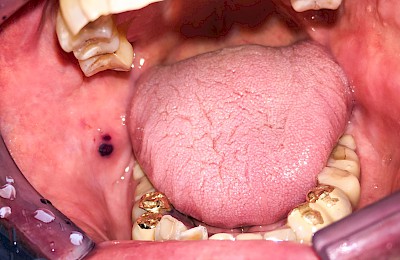

Einbiss & Bluterguss

Blutungen & Blutergüsse sind in den meisten Fälllen als ein Zeichen einer Verletzung wie z.B. einem Einbiss oder nach einem Sturz zu werten.

Blutpunkte (z.B. Petechien), Blutblasen (z.B. Hämangiome) & rote Flecken (z.B. Ausschlag) haben in der Regel eine längere Entstehungsgeschichte und sind häufig nicht auf eine direkte kurzzeitig zurückliegende Verletzung zurückzuführen.